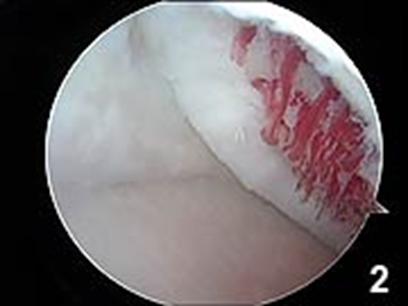

Chirurgul trebuie sa fie foarte atent atunci cand examineaza posteriorul condililor femurali. Daca se semnaleaza orice vatamare/rana/deteriorare pe suprafetele articulare, trebuie sa se cerceteze atent calitatea cartilajului. Orice flapsuri instabile sunt inlaturate prin folosirea unui aparat de ras electric artroscopic sau curette. Apoi, un curette este folosit pentru a debrida stratul de cartilagiu calcifiat de la baza in toata grosimea defectului. Acest pas se bazeaza pe activitatea lui Frisbi, care a demonstrat vindecarea suprafetei articulare superioare la un cal, cand stratul cartilagiului calcifiat este indepartat. Cand indepartam stratul cartilajului calcifiat, in general nu se foloseste un aparat de ras. Cu un aparat de ras este dificil de controlat cantitatea de os eliminat, si este posibil ca osul subcondral sa fie afectat.

Dupa indepartarea cu succes a stratului de cartilaj calcifiat, o andrea este folosita pentru a face mai multe gauri mici (mirofracturi) in osul expus al defectului condral aflate la distanta de 1-2 mm. Trebuie lasata o punte de oase potrivita intre gauri. Tehnica de microfracturi are numeroase avantaje fata de foraj. Mai intai de toate, creaza o leziune termala mai mica. Mai mult, cu microfracturi chirurgul este capabil sa intre in zonele dificile ale suprafetei articulare cu un control mai bun asupra adancimii de patrundere. La finalizarea microfracturii, o suprafata aspra este generata pentru aderenta cheagului de sange care contine celule mezenchimale nediferentiate de la osul subcondral. Trebuie avut grija ca cele mai marginase parti ale leziuni sa fie patrunse de andrea pentru a ajuta la vindecarea tesutului reparator la imprejmuirea suprafetei articulare. Odata ce microfractura este finalizata, pompa artroscopica este oprita pentru a se asigura ca sangerarea maduvei curge din gaurile mici umpland defectul.[54]

Fig.25.a. Debridarea. Fig.25.b. Microfracturare.